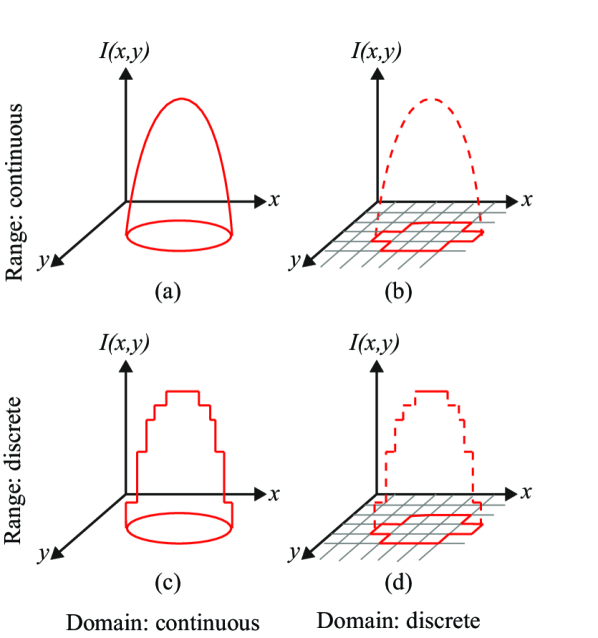

In general, a segmentation problem can be formulated in a spatially discrete or continuous domain. In the community that advocates continuous methods, it is assumed that the world we live in is a continuous world (continuous ). However, images captured by digital cameras are discrete both in space and color/intensity. The discretization in space is called sampling (discrete ) and the discretization in color/intensity or value space is called quantization. Given this categorization, we have four different cases for image representation (Figure 1).